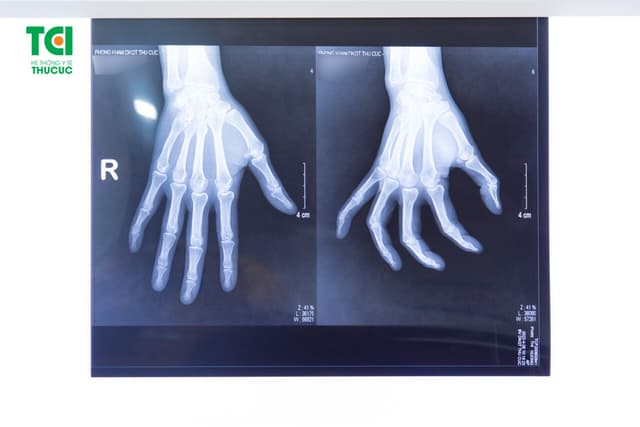

Viêm khớp ngón tay lò xo và cách điều trị

Viêm khớp ngón tay lò xo gây khó khăn cho người bệnh khi duỗi, gập ngón tay, ảnh hưởng nghiêm trọng đến cuộc sống sinh hoạt hằng ngày. 1. Viêm khớp ngón tay lò xo là gì? Viêm khớp ngón tay lò xo là tình trạng viêm bao gân cơ gấp của các ngón tay, […]